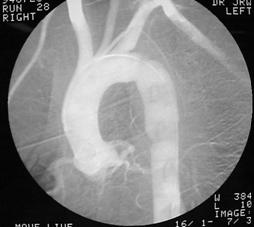

Aortograma Mediastin largit

Leziune la nivelul istmului aortic

Aortograma.Leziune

situata distal de Aorta

clampata

emergenta arterei subclavii stangi Segment

lezat excizat